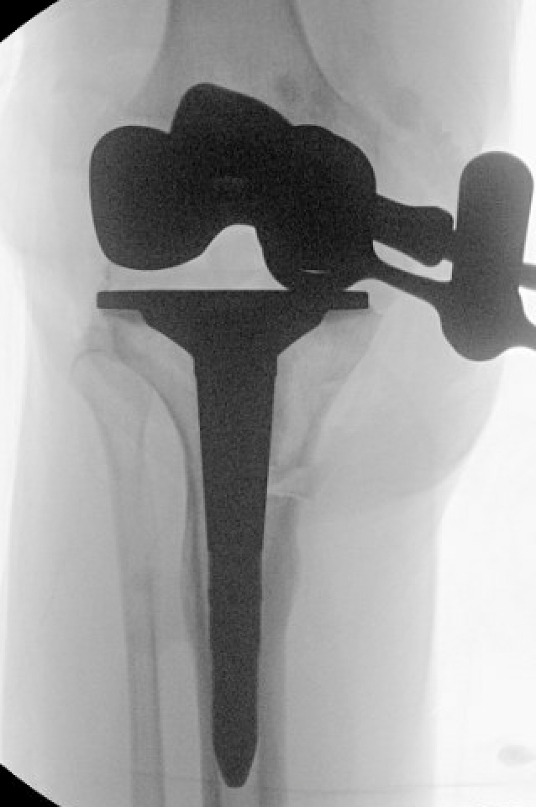

The two TTO cortical screws were removed. Attention then turned to the extra-articular deformity. Under biplanar fluoroscopic control an oblique medial open-wedge osteotomy was created six centimeters distal to the tibial plateau at the apex of the varus malunion (Figure 3). A laminar spreader was gently inserted and opened until a neutral mechanical hip–knee–ankle axis was achieved, as confirmed with an extramedullary alignment rod extending from the center of the femoral head to the center of the ankle mortise.

Trial components were inserted and demonstrated balanced flexion and extension gaps and central patellar tracking without the need for lateral release. The tibia was subsequently punched after confirming appropriate rotation for adequate patellar tracking. Final implantation proceeded with pressurized cement for the posterior-stabilized femoral component and the tibial baseplate under tourniquet insufflation. The diaphyseal press-fit stem was again confirmed to span the osteotomy by more than two cortical diameters under fluoroscopic guidance (Figure 4). Autogenous cancellous graft harvested from the femoral chamfer cuts was tightly packed into the osteotomy gap and along the medial cortex. The patella was resurfaced with a medialized polyethylene button.